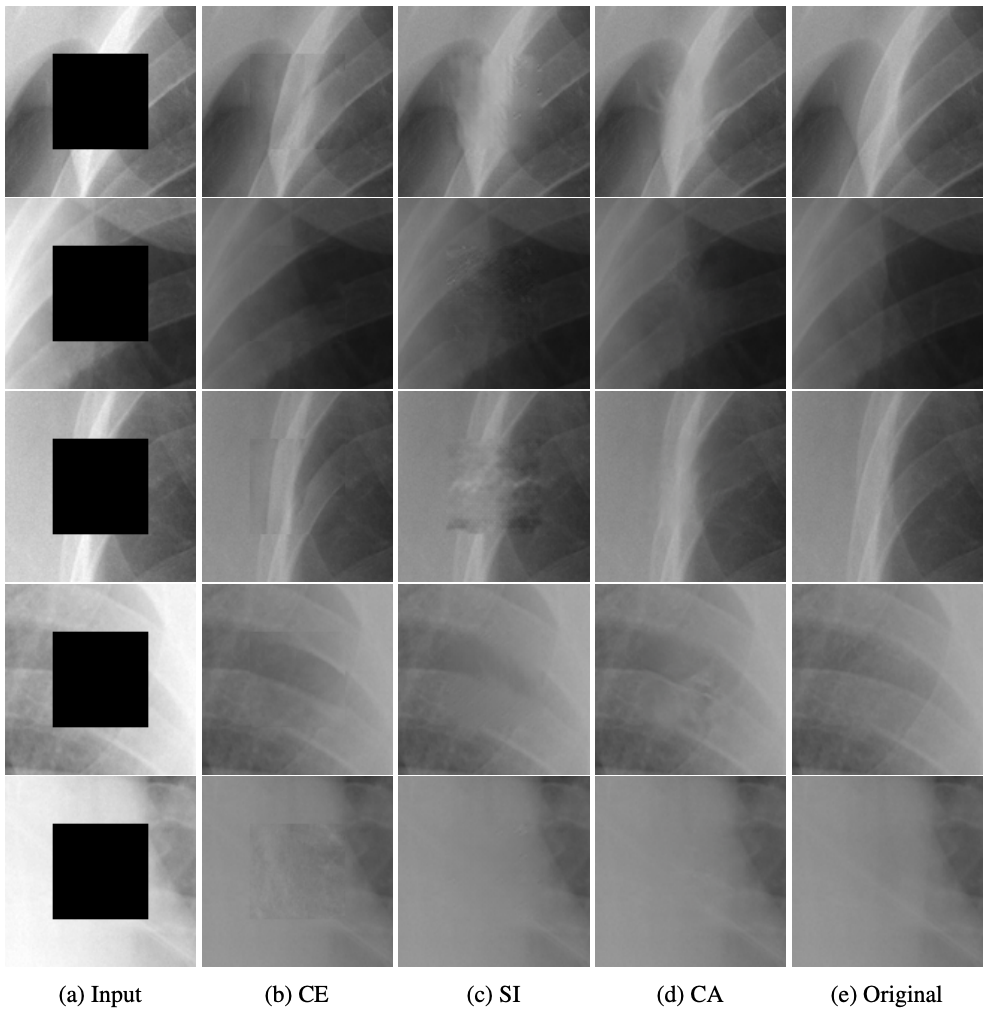

Context Encoding Chest X-rays

2018

D Belli, S Hu, E Sogancioglu, B van Ginneken

arXiv preprint

Chest X-ray Inpainting

E Sogancioglu*, S Hu*, D Belli, B van Ginneken